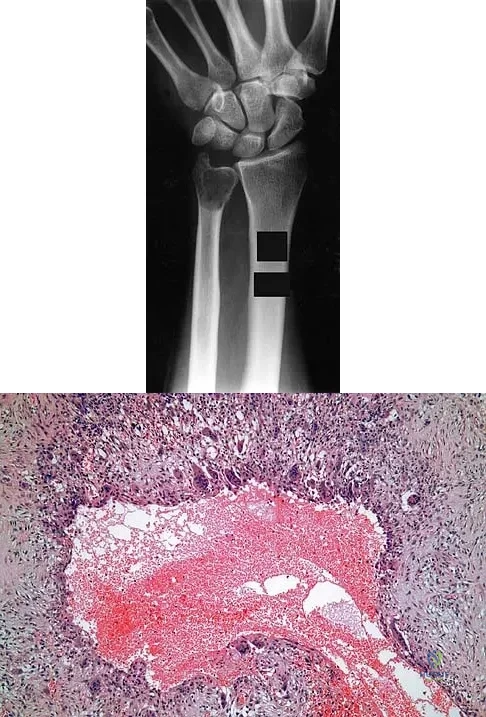

A 30-year-old patient has wrist pain. A radiograph and biopsy specimen are shown in Figures 34a and 34b. What is the most likely diagnosis?